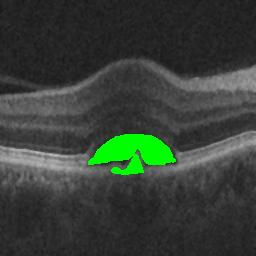

The qualitative results of the proposed system is shown in the Fig. 3. The detection task is evaluated using Area Under the Curve(AUC) metric and the segmentation task is evaluated using Dice Coefficient(DC) metric and the results are presented in Table1

|

|

| (d) De-noised OCT slice | (e)Predicted fluid region | (f)Manual fluid segmentation |

|

|

|

| (g) De-noised OCT slice | (h)Predicted fluid region | (i)Manual fluid segmentation |